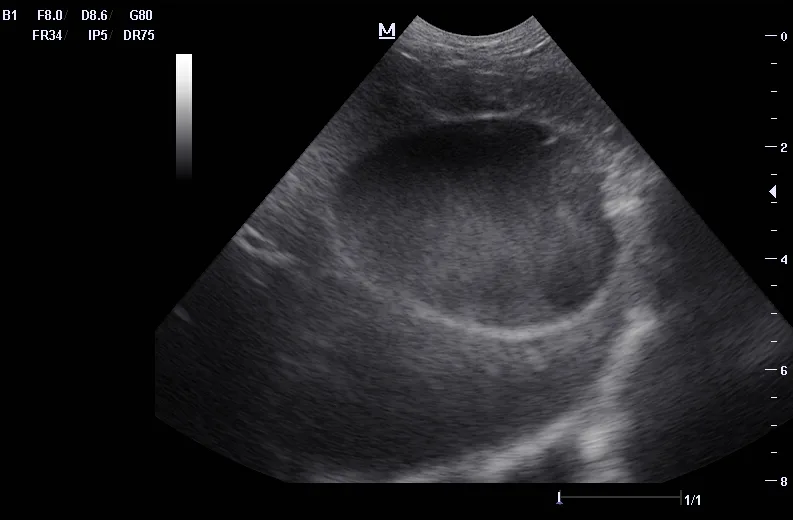

Ultrasound can be useful in evaluating the size, contour, and internal architecture of the prostate. A normal prostate appears homogeneous (Figure 1). The prostate becomes heteroechoic as a result of inflammation, hyperplasia, and neoplasia (Figure 2). The prostatic parenchyma can be focally or diffusely hypoechoic in cases of acute prostatitis or prostatic abscessation (Figure 3), as well as hyperechoic in cases of chronic prostatitis (Figure 4).

Ultrasound image of a canine prostate with small cysts.

FIGURE 2

Hyperplastic prostate with a heteroechoic appearance due to the presence of many small cysts